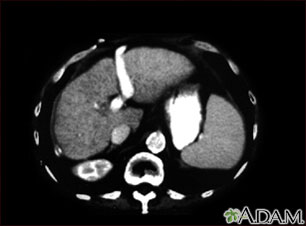

A CT scan of the upper abdomen showing cirrhosis of the liver.